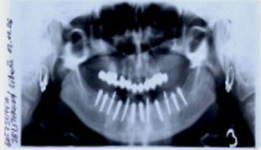

Bezzubá čelist je hlavní indikací pro ošetření pomocí implantátů. Zejména celkové zubní náhrady v dolní čelisti mají velice nízkou stabilitu a držení díky velkému úbytku kosti.

S pomocí zubních implantátů můžeme díky různým kotevním systémům (třmeny, kulové hlavy, Locatory) zajistit stabilitu a držení protézy nebo při použití většího počtu implantátů zhotovit pevné náhrady – můstky nalepené nebo našroubované na pevno na implantáty.